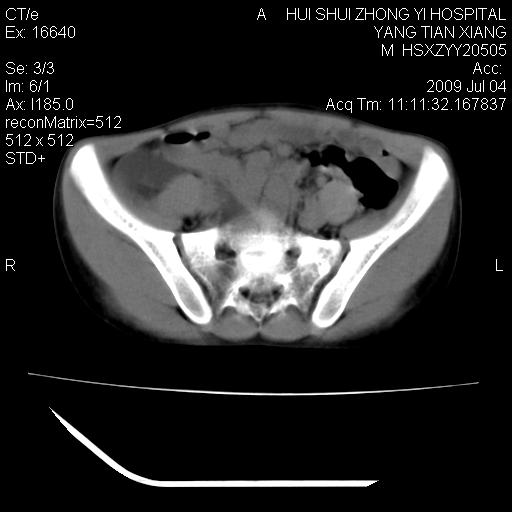

肝右叶胆管内见条状高密度影,脾脏增大,双肾上腺无异常;右肾正常结构消失,其实质内见类圆形低密度灶,ct值范围0-6hu,界清,右输尿管全程伴行多发低密度灶,界清,膀胱壁增厚,腹盆腔未见确切肿大淋巴结。

考虑:1、肝内多发胆管结石并肝内胆管扩张。2、右肾、输尿管多发脂肪瘤,多发平滑肌瘤?建议ct增强检查。4、膀胱壁增厚。

膀胱壁增厚。

1)考虑右侧巨输尿管畸形。2)肝内胆管多发性结石。3)脾大。

右侧巨输尿管并神谕积水,左肾代偿性肥大,脾大,肝内胆管多发结石并胆管扩张。